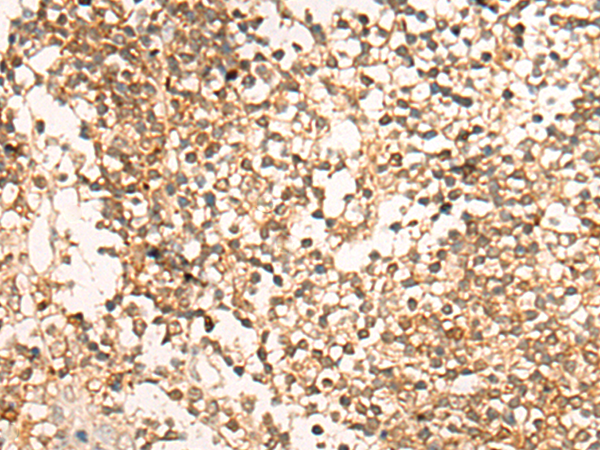

分类: 科研抗体货号: P13261别名: DSC; DSC1; DSC2; DSC4; CDHF3; HT-CP应用: IHC反应种属: Human, Mouse